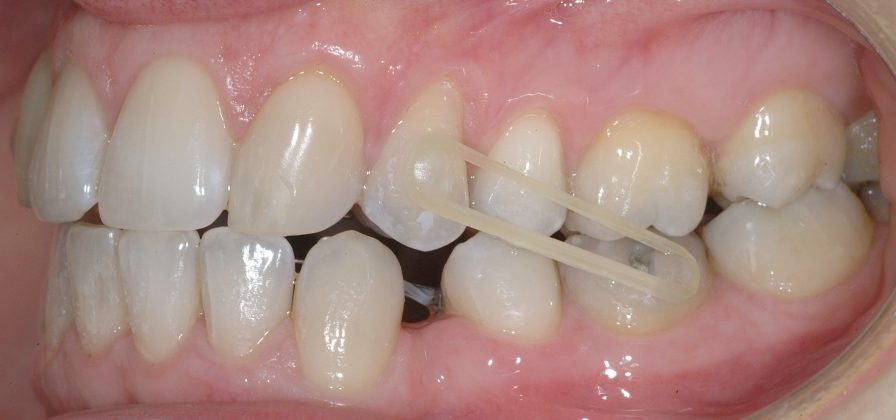

Il protocollo terapeutico ha previsto l’estrazione del primo premolare inferiore sinistro (3.4) e del primo superiore destro (1.4), l’applicazione di una apparecchiatura fissa linguale 2D e di una meccanica asimmetrica di ancoraggio e movimento ortodontico a entrambe le arcate (Figure 3a-b).

Il trattamento è iniziato con l’estrazione dei due premolari in unica seduta in anestesia locale e l’applicazione simultanea, dopo una settimana, della apparecchiatura linguale inferiore e superiore, non essendoci problemi di overbite e potenziali interferenze in occlusione tra l’apparecchiatura superiore e i frontali inferiori. All’arcata superiore è stata effettuata una iniziale chiusura dello spazio estrattivo con forze molto leggere in ancoraggio medio su arco .014” Nichel-Titanio e successivamente .016” Nichel-Titanio, bondato in prima fase per maggior stabilità direttamente sulla superficie mesiale di 2.4.

Nota tecnica: il movimento iniziale di distalizzazione della corona di 1.3 mediante tipping distale (vista la posizione radicolare iniziale) è stato ottenuto con una catenella elastica leggera inserita su 1.6, 1.5 e ancorata su 1.3, abbracciando per maggior controllo l’aletta disto-occlusale e quella gengivale del bracket linguale.

Per completare la chiusura degli spazi inferiori in ancoraggio medio è stata applicata una catenella elastica leggera da 3 a 6 ed elastici di Classe II (3/16 da 4.5 once) bilaterali e domiciliari-notturni, applicati vestibolarmente su bottoni estetici bondati su 3.6, 4.6, 1.3 e 2.4 (Figure 7a-e).